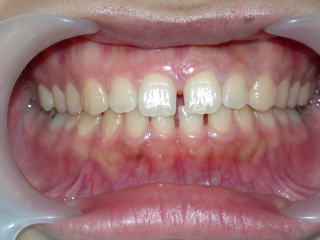

術前平成25年2月12日、いわゆるすきっ歯が気になるそうです。